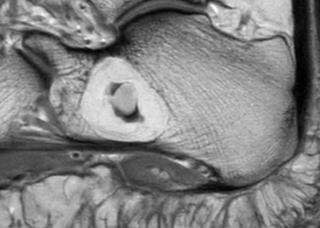

| MRI | T1強調像:高信号(脂肪成分)/T2強調像:高信号/脂肪抑制像で低信号化。内部壊死部は不均一。 |

| 特徴的サイン | 「中心部石灰化+周囲に脂肪信号」のリング状像。 |

⚠️ MRIで脂肪抑制後も高信号を示す場合は脂肪腫以外(脂肪肉腫・線維腫様変化など)を疑う。